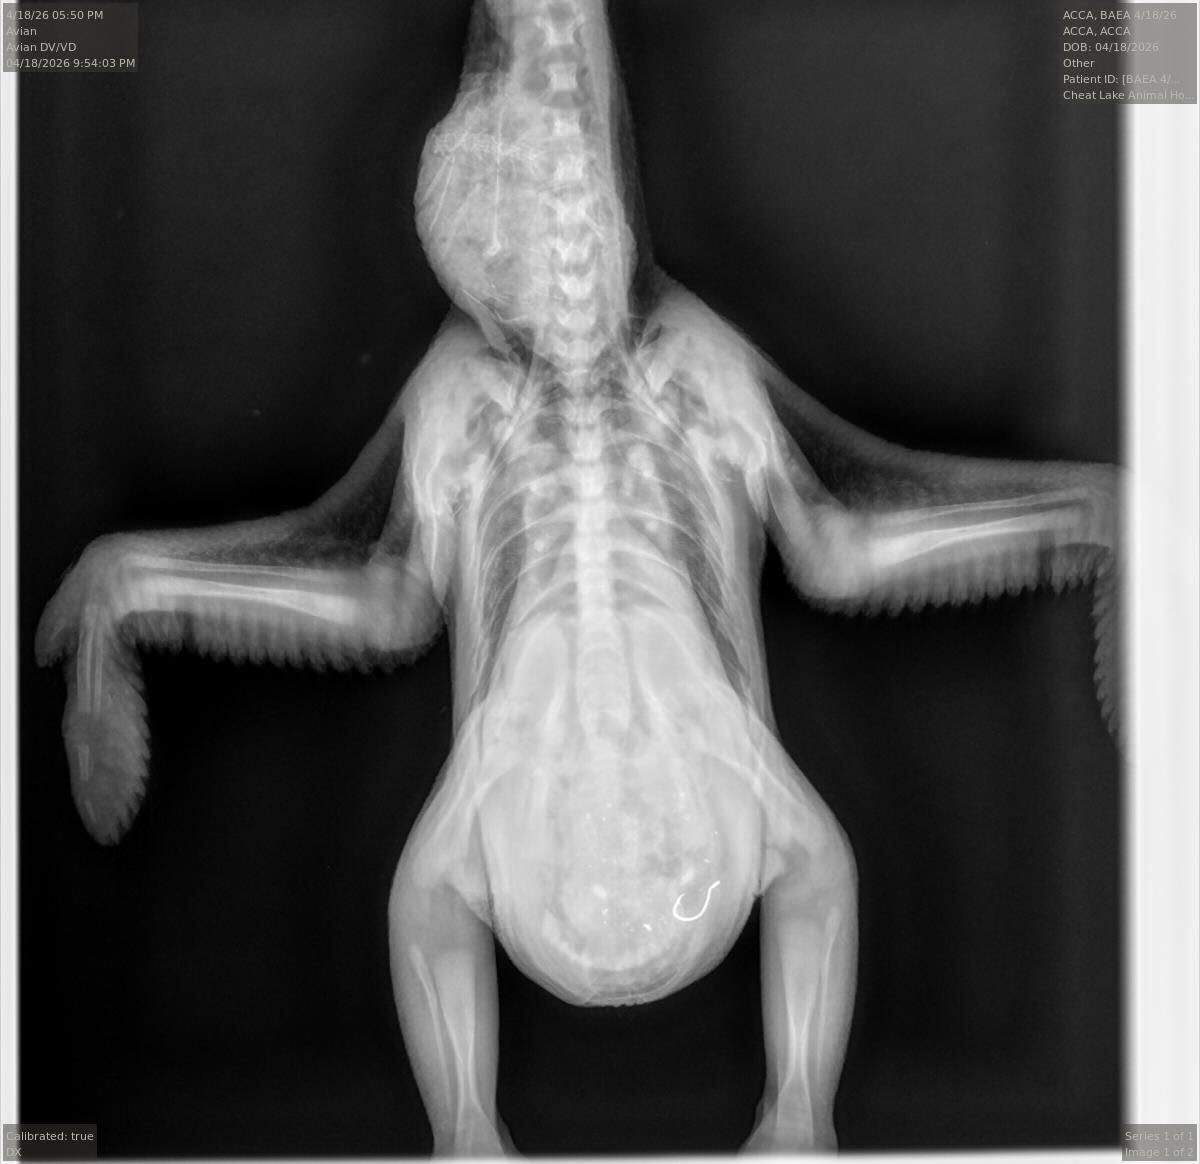

An X-ray of the eaglet, showing the fishhook in its stomach.

(Dr. Jesse Fallon/Avian Conservation Center of Appalachia / FOX Weather)

The eaglet's X-ray, showing the fishhook in its stomach.